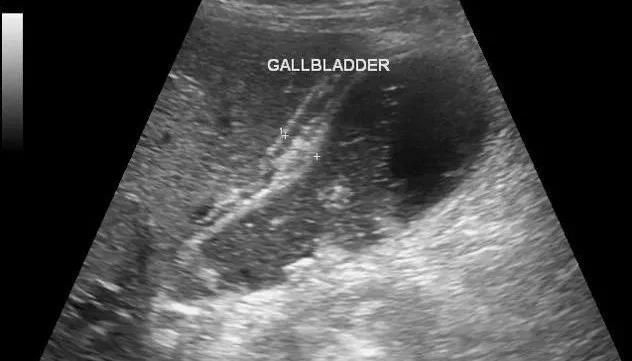

▲正常胆囊壁显示为线状强回声带,走行自然,光滑平整,厚度<3mm